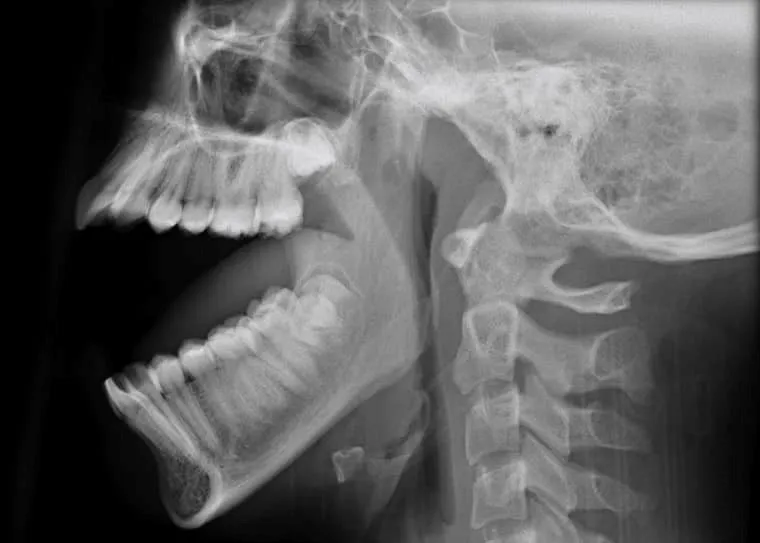

trật khớp hàm.jpg

Thanh niên 27 tuổi bị trật khớp hàm sau khi ngáp lớn. Ảnh: TTYT Phù Ninh

Sau khi thăm khám, các bác sĩ phát hiện bệnh nhân bị trật khớp thái dương - hàm hai bên.

Theo bác sĩ Đỗ Xuân Hùng, Trưởng khoa Ngoại - Trung tâm y tế huyện Phù Ninh, trật khớp thái dương - hàm là sự mất tương quan giải phẫu bình thường giữa lồi cầu xương hàm dưới và lồi khớp xương thái dương. Nếu không điều trị kịp thời dễ dẫn đến cứng khớp, giãn dây chằng không hồi phục.